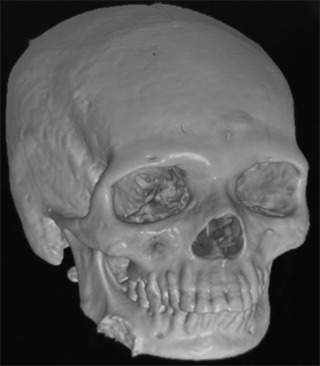

异位甲状腺是一种罕见的先天性异常,是由于胚胎发生阶段盲肠孔到原始甲状腺的管道失败而导致的。具体患病率为10 -30万分之一。发育、遗传和突变在异位甲状腺的形成中起作用。异位甲状腺最常见的位置是舌底,其次是下颌下、气管前、食管、纵隔、隔膜和其他罕见的部位。另外,侧异位甲状腺是一种罕见的临床疾病,它是由于甲状腺外侧部分未能下降到中线而形成的,正常解剖位置的正常甲状腺。在这里,我们提出一个病例报告的外侧异位甲状腺,通常不闪作为一个无痛的诊断标题,坚定的肿块在下颌骨的侧面,使治疗计划不确定。临床,放射学,实验室检查和组织病理学检查对异位甲状腺进行分类和最终治疗。定期随访并保持甲状腺功能正常,为患者提供了珍惜和积极的输出。

Ectopic thyroid is a rare congenital anomaly that results from failure of decent from the foramen cecum to the primitive thyroid during the stage of embryogenesis. The specific prevalence ranges from 1 in 100,000-300,000 population. Development, genetics, and mutation play a role in the formation of ectopic thyroid. The most common location of ectopic thyroid is at the base of the tongue, followed by sub-mandibular, pre-tracheal, esophageal, mediastinum, diaphragm, and other rare sites. Lateral ectopic thyroid is further a rare clinical entity which is formed due the failure of descend of the lateral thyroid component to the midline with a euthyroid in its normal anatomical position. Here, we present a case report of lateral ectopic thyroid which ordinarily does not flash as a diagnosis title for a painless, firm mass on the lateral aspect of the mandible, making the treatment plan inconclusive. Clinical, radiographic, laboratory tests with a histopathalogical examination make a categorical and final treatment for the ectopic thyroid. Regular follow-up with a euthyroid state maintenance gives a cherishing and positive output for the patient.